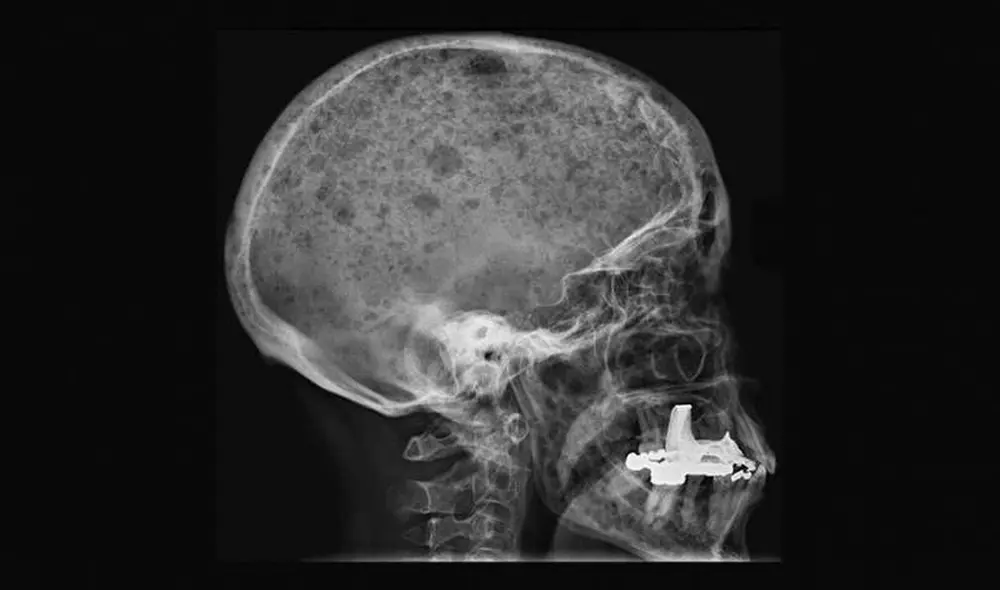

A este anticuerpo le faltan dos moléculas de azúcar, lo que ocasiona que el esqueleto se quiebre | Foto: Therese Standal / NTNU